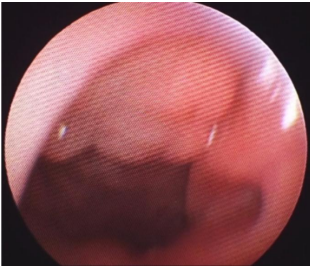

Mulher, 56 anos de idade, tabagista há 25 anos, refere rouquidão progressiva nos últimos 6 meses, associada à voz soprosa e fadiga vocal, além de dispneia aos esforços moderados. Nega disfagia ou perda ponderal. Nega história de trauma laríngeo. Ao exame, encontra-se eupneica em repouso. A avaliação vocal demonstra voz rouca, grave e soprosa. A videolaringoscopia em abdução mostra os achados apresentados na imagem a seguir:

Enunciado 4540959-1

Além de medidas antitabagismo, qual é a melhor conduta terapêutica?